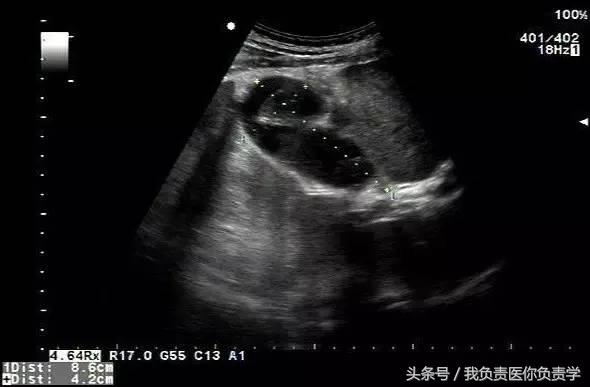

典型病例 4

患者女,79岁,晚餐后出现脐周疼痛数小时急诊。患者无发热,实验室检查示白细胞14×109/L,临床考虑阑尾炎,行超声检查所见如下:

图1示胆囊充盈差,囊壁明显增厚,胆囊周围可见无回声环绕分布

图2为高频探头所见,示胆囊壁肝床侧回声中断,周围可见无回声分布

超声诊断为胆囊穿孔,后经手术证实。